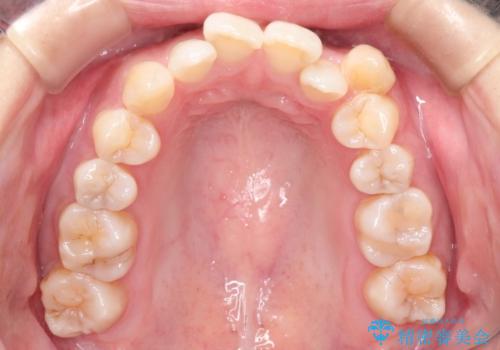

前歯の叢生があり、上下の前歯が接触していない開咬という状態でした。

左側の上下の前から4番目の歯を抜歯して、矯正することとしました。

装置は表側のワイヤーを選択されました。